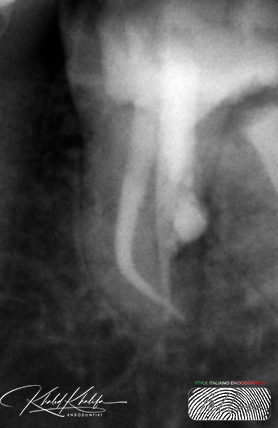

Unfortunately, in this case as you can see, the previous doctor tried to retrieve/bypass the file before referring the case as seen in the first 2 photos they made a perforation above the broken file in inner wall.

Broken File Retrieval + Managment of Acute Curve + Sealing Perforation and Coronal part of the root with Bioceramic Material.